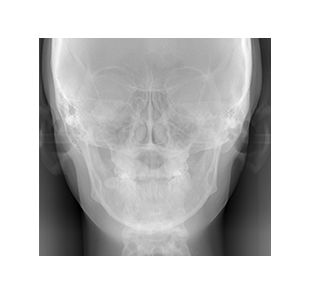

レントゲン写真を元に、

歯並びと顎骨の分析をします

矯正カウンセリングにお越しいただいた方を対象に、WEBCEF(ウェブセフ)よる歯列矯正の解析レポートを作成し、詳しいご説明の上でご提供します。

この解析レポートでは、

・歯並びの左右の傾き

・お顔の中心に対して上顎歯列と下顎歯列がずれていないか

・ずれている場合には、どのように改善できるか

などを分析します。

レントゲン写真を元にして

実際に解析された画像

こちらの分析では上顎前歯と下顎前歯のどちらも右側にずれていることがわかります。

このズレを矯正治療によって、正常な範囲まで移動させて治します。